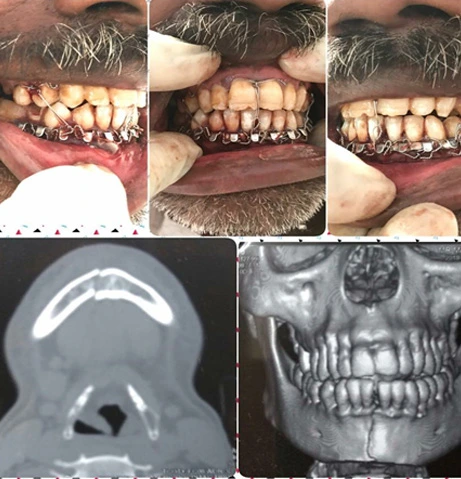

Maxillofacial Trauma care:

Surgical management of fractured facial bones

• Complex fractures are managed by Open Reduction and Internal Fixation under GA in Major OT.

Simple fractures are managed by Closed Reduction and Intermaxillary Fixation with arch bar and eyelet under LA in Minor OT

Responsive Image